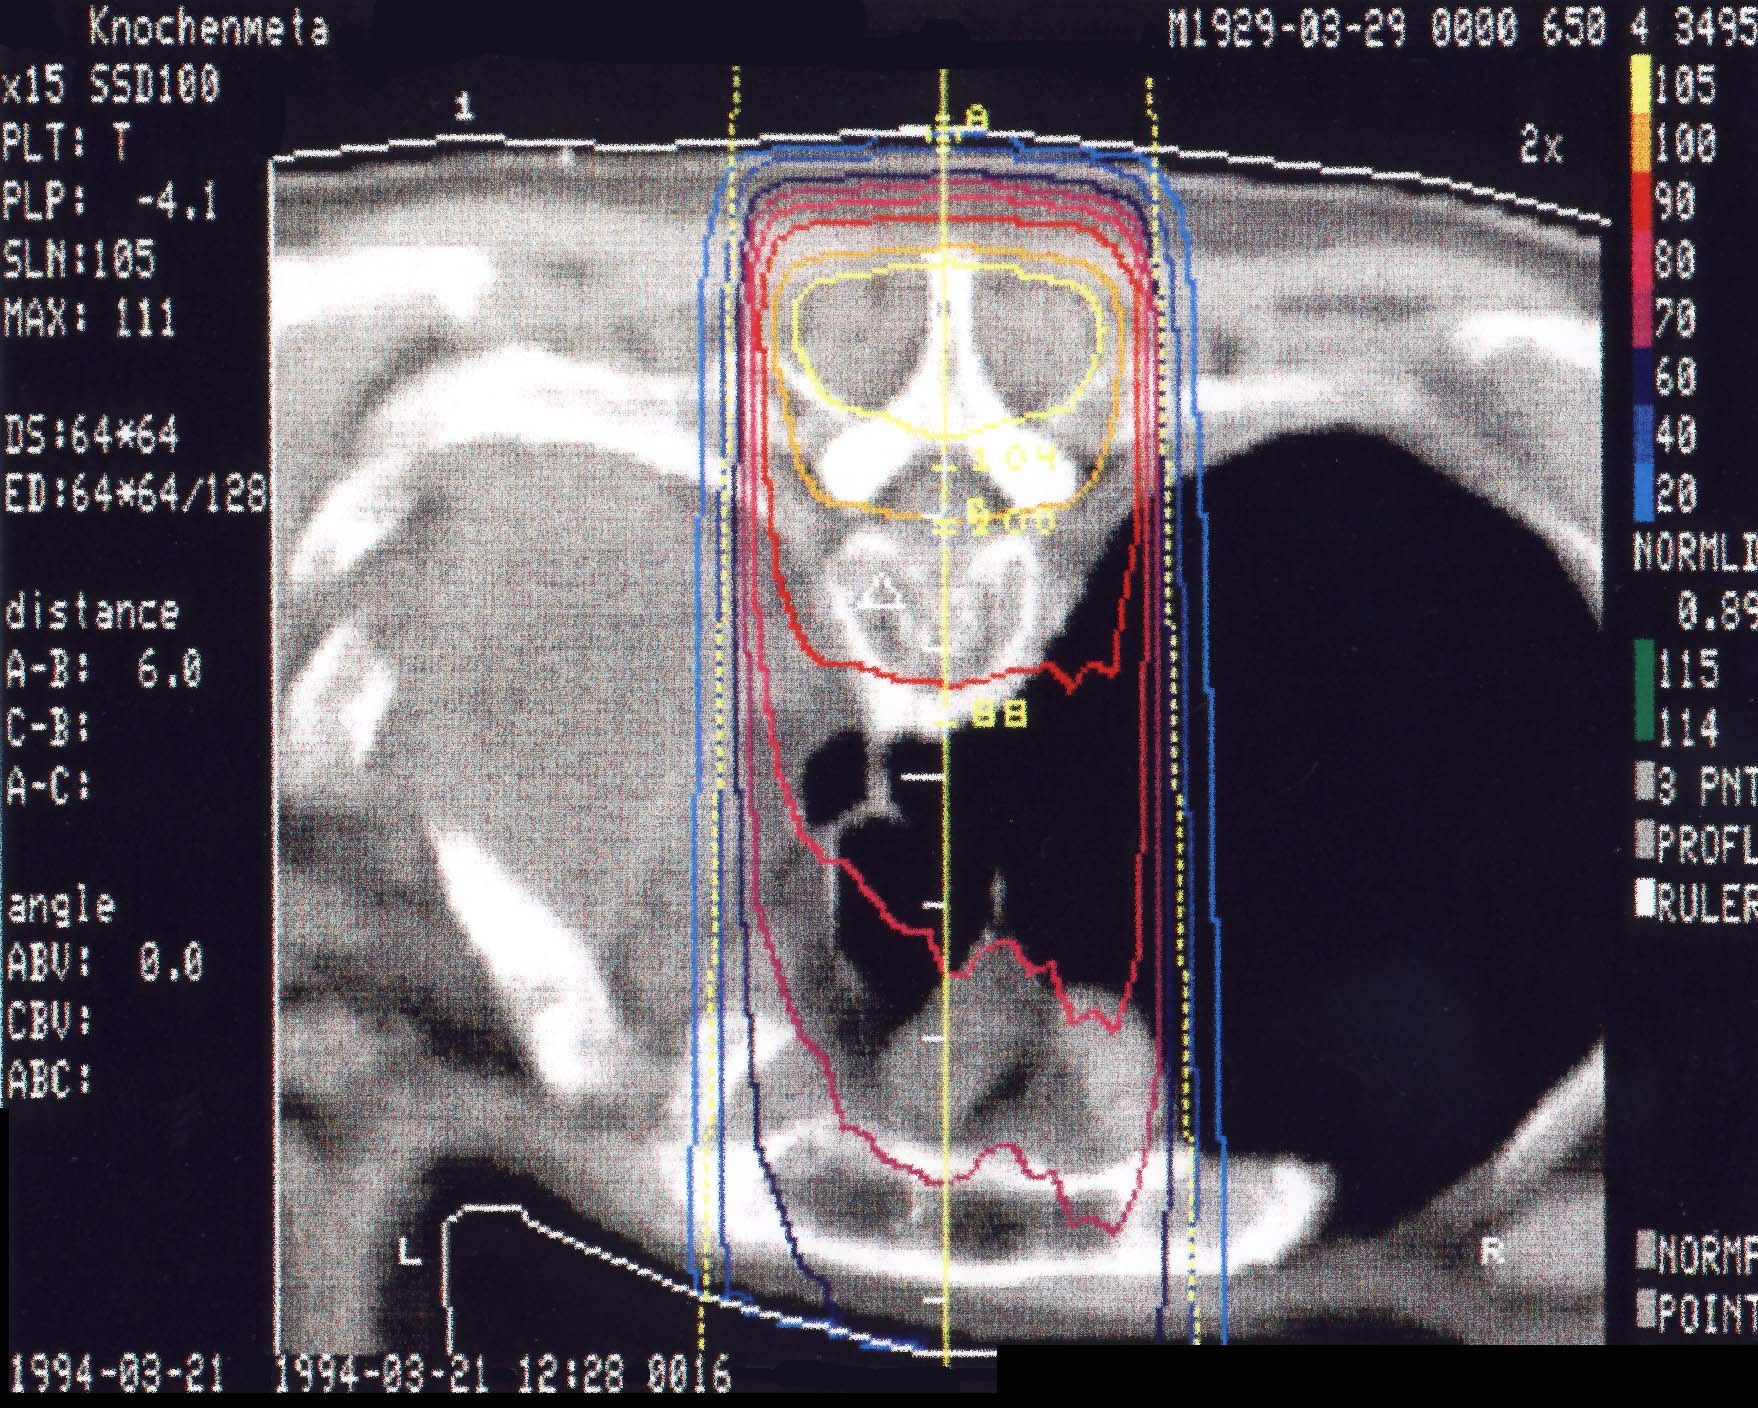

Tumore des Knochens: Bestrahlungsplan

Einführung aktuelle Bilder - Einführung Bestrahlungspläne - Einführung Demonstration